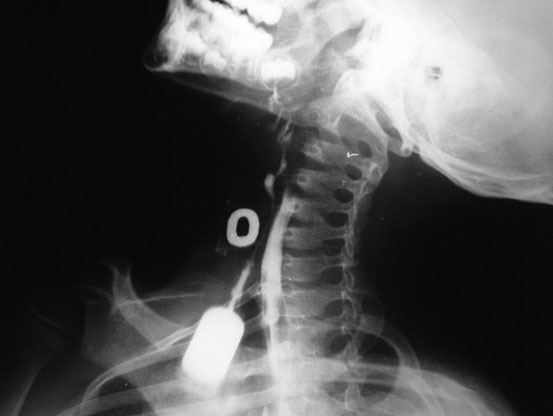

Röntgenaufnahme des Jungen aus dem Titelbild. Mit Kontrastmittel lässt sich der Fistelgang im gesamten Verlauf vom Hals bis zur Mundhöhle nachweisen. Die Fistelgänge werden in voller Länge entfernt, um Infektionen und Zystenbildung zu vermeiden.